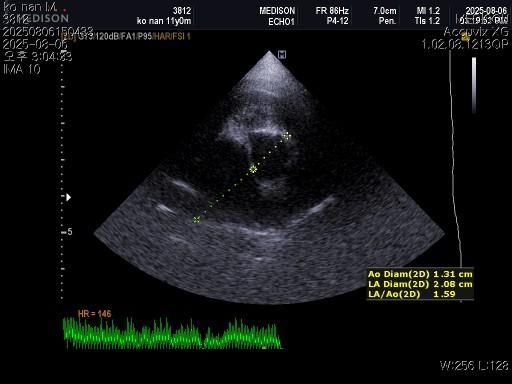

1) 혈액검사와 엑스레이 그리고 초음파상 혈뇨의 원인이 나타나지가 않는지 궁금합니다.

2) 그리고 전립선 비대가 있는지도 없는지 여부가 궁금합니다.